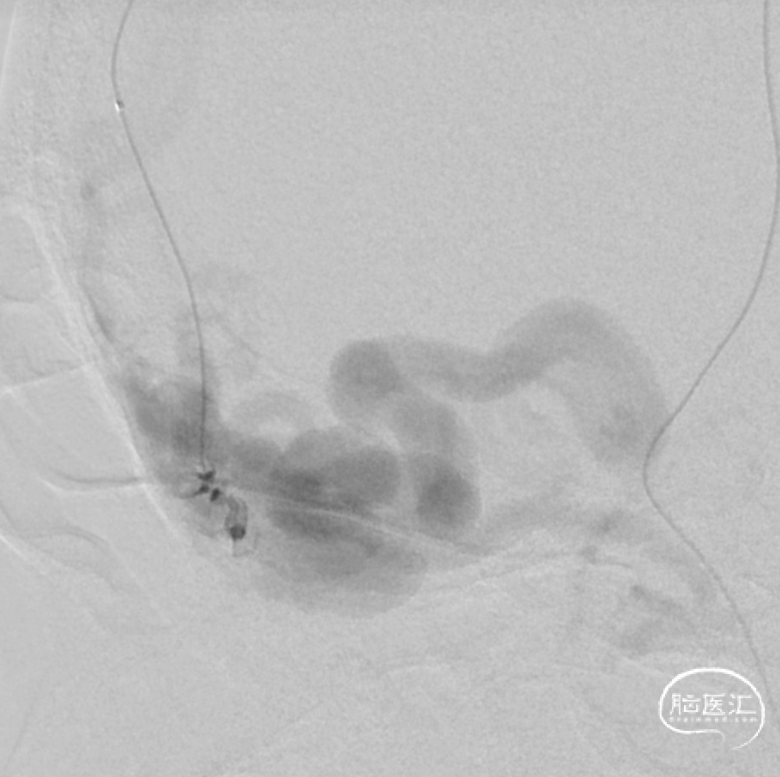

一期治疗

二期治疗